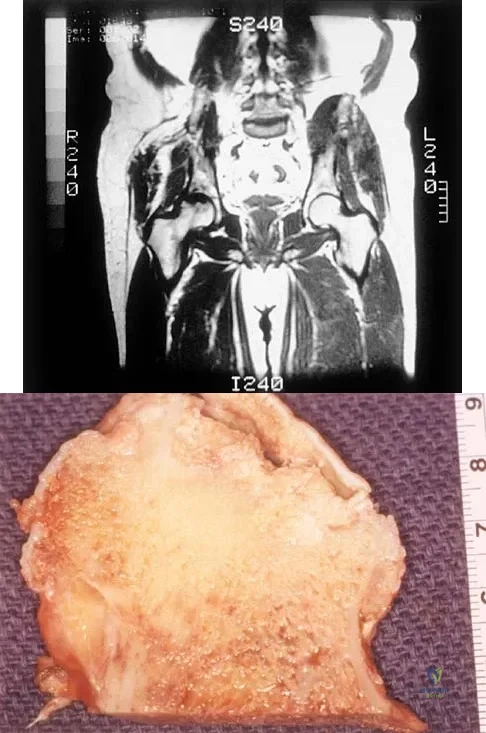

A 35-year-old patient has right hip pain. Figures 34a and 34b show the coronal MRI scan and the biopsy specimen. What is the most likely diagnosis?

Explanation